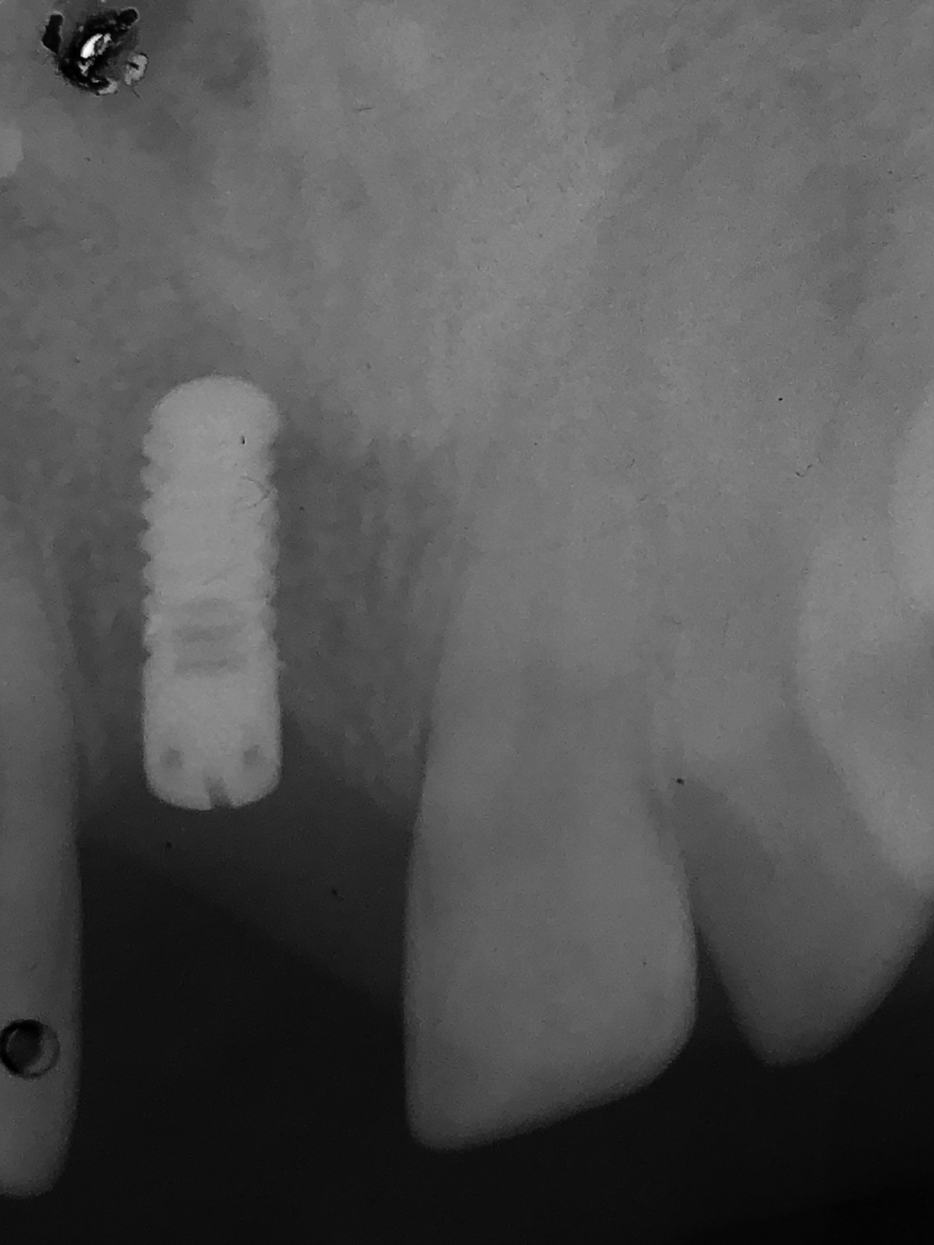

An implant with a diameter of 3.7 mm and a length of 12 mm was inserted in November 2001. A follow-up X-ray was taken 5 months after implantation.

After the implant healed, a metal-ceramic crown was fitted in June 2002. No objective or subjective changes were noted during regular recalls. Follow-up X-ray was taken in January 2003.